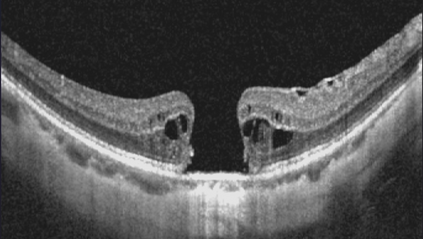

Ophthalmology relies heavily on detailed image analysis for diagnosis and treatment planning. While large vision-language models (LVLMs) have shown promise in understanding complex visual information, their performance on ophthalmology images remains underexplored. We introduce LMOD, a dataset and benchmark for evaluating LVLMs on ophthalmology images, covering anatomical understanding, diagnostic analysis, and demographic extraction. LMODincludes 21,993 images spanning optical coherence tomography, scanning laser ophthalmoscopy, eye photos, surgical scenes, and color fundus photographs. We benchmark 13 state-of-the-art LVLMs and find that they are far from perfect for comprehending ophthalmology images. Models struggle with diagnostic analysis and demographic extraction, reveal weaknesses in spatial reasoning, diagnostic analysis, handling out-of-domain queries, and safeguards for handling biomarkers of ophthalmology images.